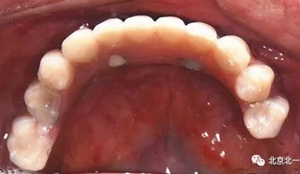

圖十八:口內(nèi)試戴鈦支架

圖十九:永久修復(fù)完成

圖二十五:口內(nèi)照。